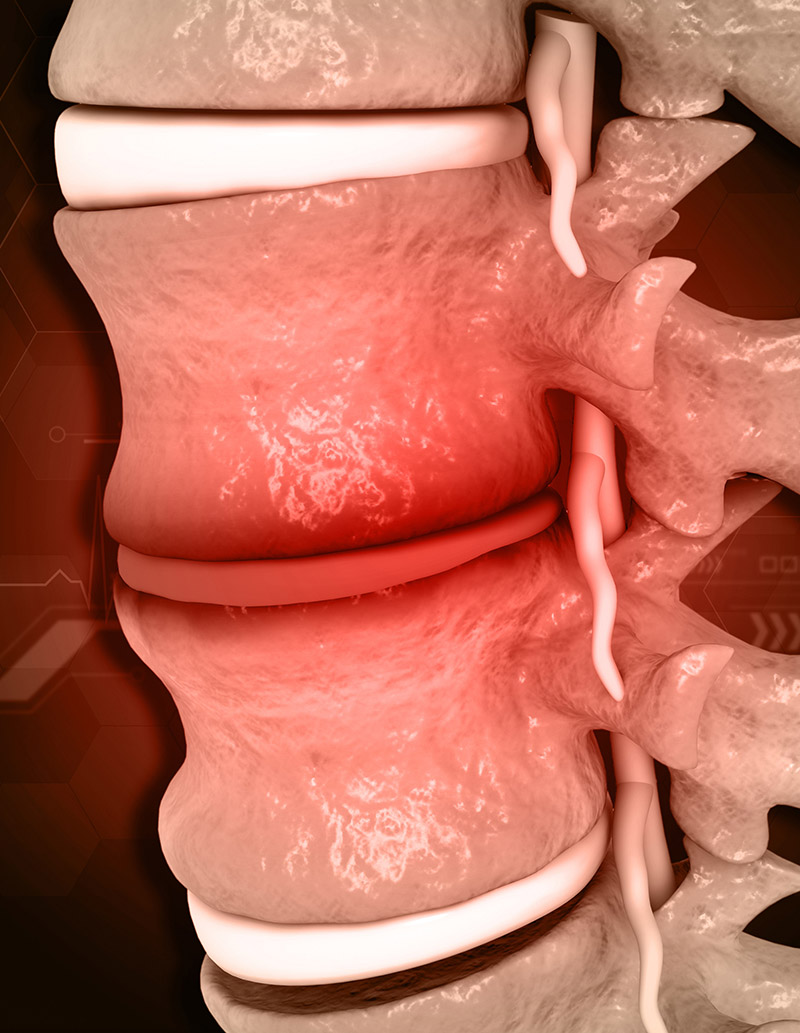

Degenerative disc disease happens when the rubbery cushions (discs) between the vertebrae begin to wear away and the vertebral bones begin to rub together.